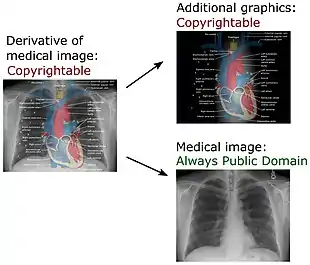

Copyright

United States

As per chapter 300 of the Compendium of U.S. Copyright Office Practices, "the Office will not register works produced by a machine or mere mechanical process that operates randomly or automatically without any creative input or intervention from a human author" including "Medical imaging produced by x-rays, ultrasounds, magnetic resonance imaging, or other diagnostic equipment."[50] This position differs from the broad copyright protections afforded to photographs. While the Copyright Compendium is an agency statutory interpretation and not legally binding, courts are likely to give deference to it if they find it reasonable.[51] Yet, there is no U.S. federal case law directly addressing the issue of the copyrightability of x-ray images.

Derivatives

An extensive definition of the term derivative work is given by the United States Copyright Act in 17 U.S.C. § 101:

A "derivative work" is a work based upon one or more preexisting works, such as a translation...[note 1] art reproduction, abridgment, condensation, or any other form in which a work may be recast, transformed, or adapted. A work consisting of editorial revisions, annotations, elaborations, or other modifications which, as a whole, represent an original work of authorship, is a "derivative work".

The copyright in a compilation or derivative work extends only to the material contributed by the author of such work, as distinguished from the preexisting material employed in the work, and does not imply any exclusive right in the preexisting material. The copyright in such work is independent of, and does not affect or enlarge the scope, duration, ownership, or subsistence of, any copyright protection in the preexisting material.